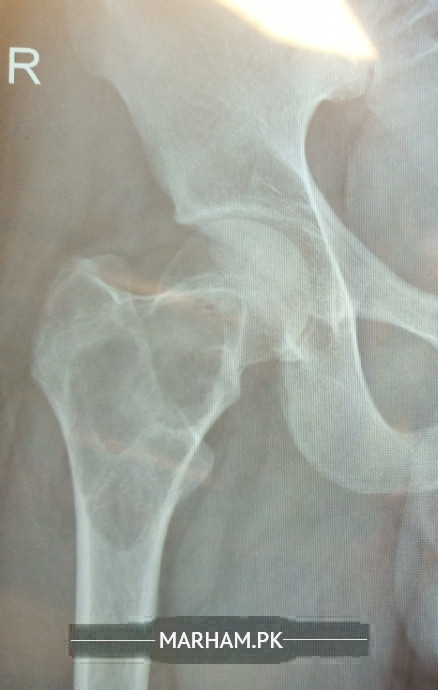

I have diagnose with abc bone tumor on right femoral nick of hip joint dr says there is no option to heal with out operation but i have studied there are series of injection to heal up the bone with out need of surgery so what should i do please there any treatment available to cure the cyst with out operation /surgery please.

The best option is to do DHS fixation with bone or bone substitute augmentation. The success rate documented is 80 to 85%.

injection therapy has high failure rate and results are dependent on size of the cyst. it is very important that all cyst in proximity of neck of femur should be prophylactically fixed with dhs, before it collapses or post fall results in fracture. This is evidence based treatment and my practice experience agrees with it

needs early fixation with DHS-lcp long side plate or PFN. before it fractures. see a senior experienced orthopedic surgeon as early as possible

needs urgent fixation with DHS plus bone substitute (bone cement or bone graft,